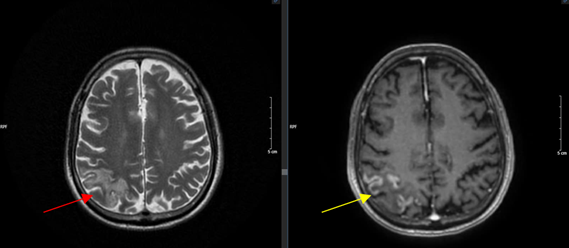

- Chụp MRI sọ não (tháng 9/2024):

Hình 4: Dày, ngấm thuốc màng não kèm theo phù não vùng chẩm P kích thước 60*40mm trên xung T2 (mũi tên đỏ), và xung T1 tiêm thuốc (mũi tên vàng)

Hình 10: Hình ảnh cộng hưởng từ sọ não trên xung T1 tiêm thuốc: hình ảnh tổn thương dày, ngấm thuốc màng nào (mũi tên vàng) sau 6 đợt điều trị không còn tổn thương ngấm thuốc màng não (mũi tên đỏ)